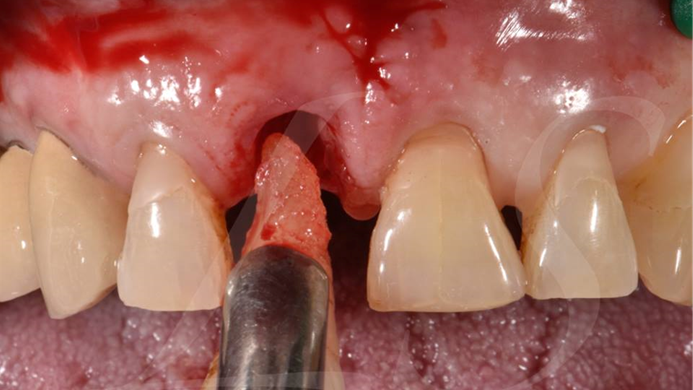

“ONE-DAY implant, one-day smile

”

Clinical case: : R2GATE guided surgery & immediate implant placement

- Courtesy of Dr. Kwang Bum Park, Korea -

Dr. Kwang Bum Park, immediate loading, digital guided surgery, digital ONE-DAY implant, maxillary anterior, #21, guided surgery, immediate loading, AnyRidge, R2GATE, Mega ISQ, MEG Torq, R2GATE Full Surgical Kit

implant system, R2GATE Guide, R2GATE full surgical kit, Mega ISQ